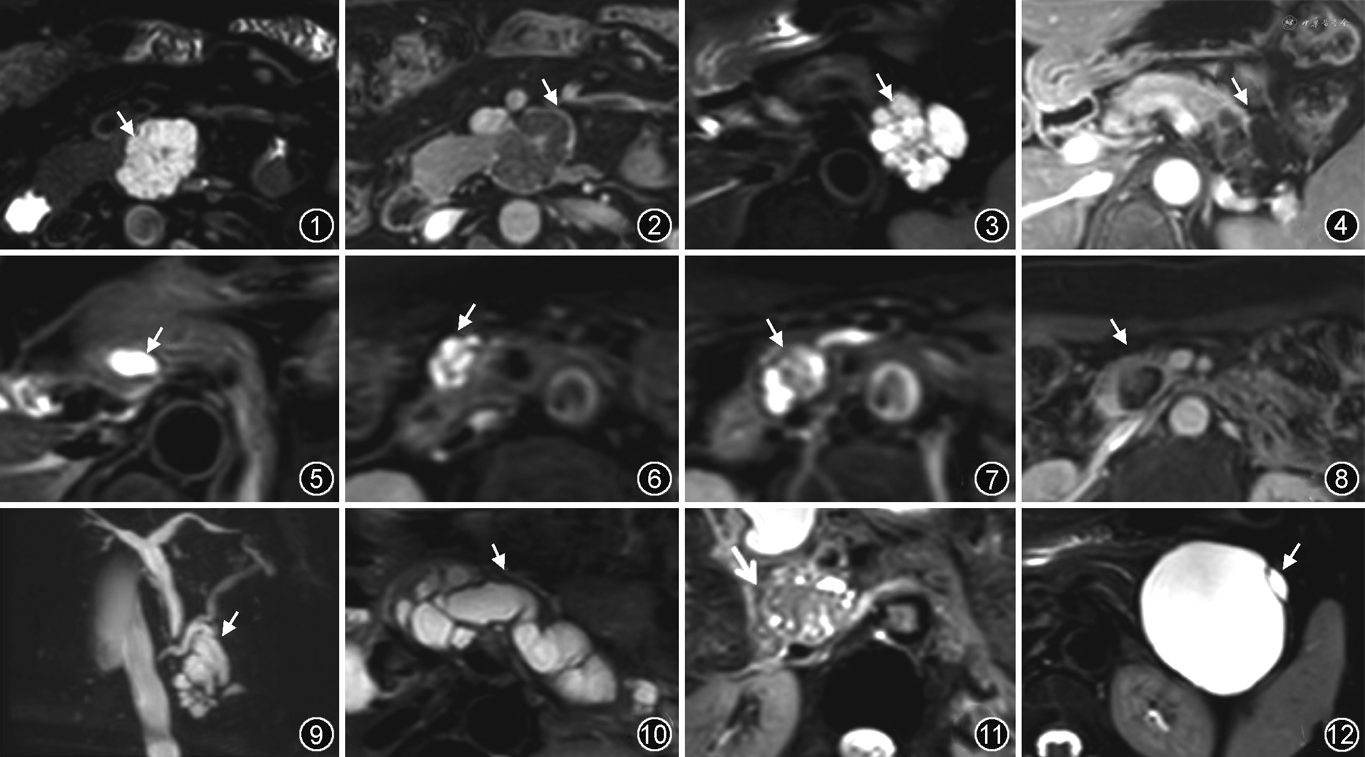

MRI影像特征:典型的PDAC最常见于胰头(60%~70%),在脂肪抑制T1WI上表现为低信号肿块,T2WI信号混杂,可呈高、稍高、等信号[2],在DWI上大部分呈高信号(图14),肿瘤内坏死囊变和出血少见[19]。增强扫描强化程度低于周围胰腺实质,动脉期尤其明显[3](图15),若增强扫描呈环形强化,提示其侵袭性更高,预后更差。胰头肿块可引起导管阻塞,伴胆总管和胰管继发性扩张,形成“双管征”(图16),肿瘤远端胰腺萎缩(图17),远端胰腺实质强化减弱[20]。随着肿瘤的生长,常会浸润胰腺周围结构,包裹邻近的血管系统或器官[2]。DWI序列提高了对较小病灶(≤3 cm)、界限不清的等信号肿块和小转移灶的检出率[4,20]。日本的一项多中心研究认为主胰管单发狭窄对早期胰腺癌的诊断有一定的提示价值[21]。PDAC需要与肿块形成型胰腺炎、局灶性自身免疫性胰腺炎(图18,19)、十二指肠旁胰腺炎或“沟槽胰腺炎”等胰腺炎性肿块相鉴别。导管穿透征(导管平滑狭窄地穿过病变)、侧支胰管扩张提示胰腺炎性肿块,胰管与胰腺实质的比值>0.34、慢性钙化性胰腺炎钙化移位、“双管征”、血管包裹或移位则提示PDAC[20]。

MRI影像特征:PACC好发于胰腺体尾部,体积常较大,以实性成分为主,可见包膜,但包膜欠完整,肿瘤常出现坏死、囊变和出血,在T1WI上多表现为混杂低信号,T2WI多呈混杂高信号,多为乏血供肿瘤,增强扫描呈渐进性强化[19],强化程度低于正常胰腺组织(图20),包膜明显强化,部分囊变灶内因有少许纤维分隔可呈轻度强化。肿瘤可累及胰管与胆管,约50%的PACC侵犯邻近器官或发生远处转移[19],此时需要与PDAC鉴别。PACC发病年龄比PDAC相对年轻[22],PACC肿瘤体积较PDAC大,PACC和PDAC虽同为乏血供恶性肿瘤,但其强化程度高于PDAC,且PACC常出现囊变、坏死、出血。

MRI影像特征:SPNP多发生于胰腺体尾部,典型表现为大的、孤立的、边界清楚的病变,可表现为完全囊性、囊实混合或纯实性肿块,囊性与实性成分的比例与肿瘤退变程度有关,部分钙化,可伴有较厚的纤维化假包膜[24]。实性成分在T1WI上呈中等信号,T2WI上呈稍高信号,DWI呈稍高信号。瘤内囊变、出血多见(图21)。增强扫描实性部分动脉期呈轻度不均匀强化,门静脉期及延迟期呈填充式强化,但强化程度仍低于正常胰腺组织。SPNP周围的纤维包膜在T1WI和T2WI上均呈低信号[23],增强扫描动脉期轻度强化,门静脉期及延迟期强化程度增加(图22)。包膜和肿瘤内出血是诊断SPNP的重要线索。SPNP与有包膜的PACC鉴别困难,边界清晰、体积较大、好发囊变及出血、实性部分渐进性强化均是二者的共同特征,PACC好发于中老年男性,发病年龄及性别有一定的鉴别意义。

MRI影像特征:pNET的典型外观是直径1~5 cm、边界清晰的单发肿块[25]。T1WI呈低信号,T2WI呈中高信号,经常具有丰富的血管,在DCE-MRI上,动脉期呈明显强化(图23),在动脉增强晚期,明显强化的病灶与中度强化的正常胰腺对比显著[2],如果肿瘤中含有纤维化成分,则会出现延迟强化。ADC值与肿瘤分级有相关性,肿瘤级别越高,扩散受限越严重,DWI信号越高(图24),ADC值越低。而高达50%的pNET不表现为动脉期明显强化,而是表现为静脉期等强化或明显强化。动脉期和静脉期低强化的pNET可能是更高级别的,难以与PDAC鉴别[25]。10%~20%的pNET可表现为部分或全部囊性病灶,大多数囊性pNET比实性pNET体积更大,通常无功能,可能比实性病变预后更好。动脉期明显增强的厚壁是pNET的特征性表现(T2WI信号均匀,壁平滑,外周增强),需要与坏死性腺癌鉴别(T2WI信号不均匀,壁不规则,外周和中央都可以增强)。囊性pNET还需要和MCN鉴别,MCN通常发生在60岁左右的女性,表现为大单囊,壁增厚强化[25]。